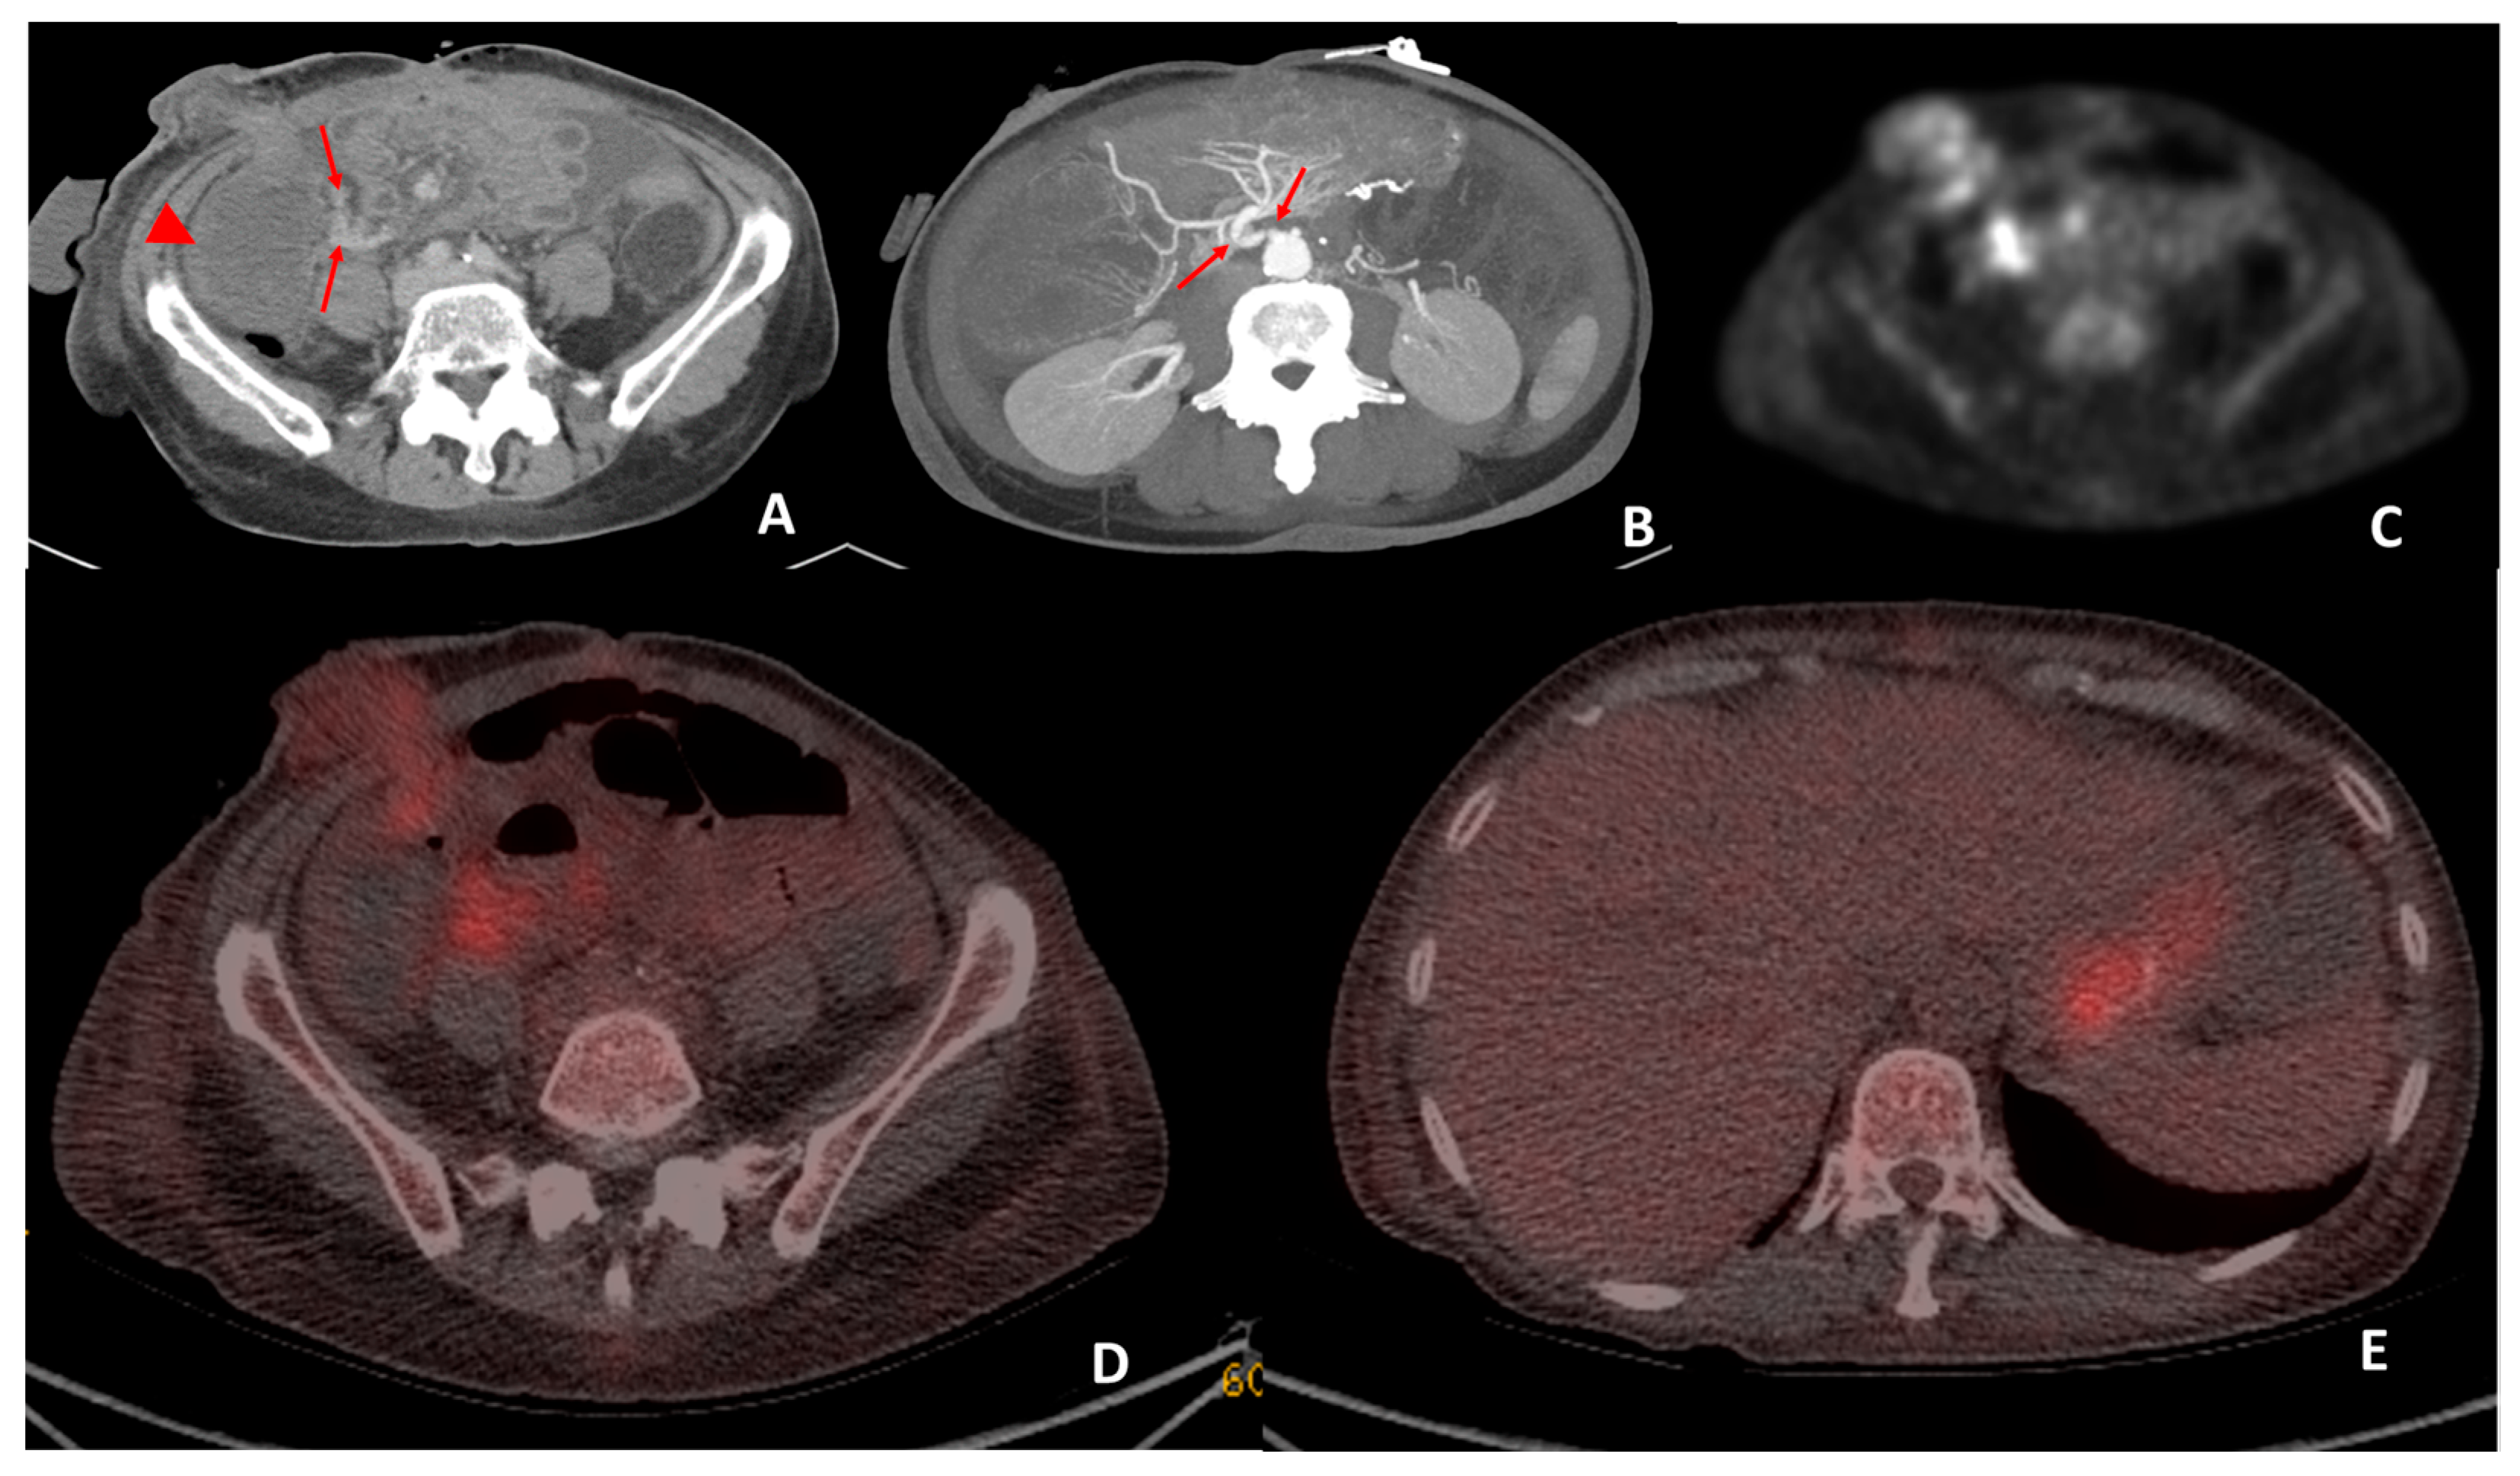

3.5. Rejection

There were three patients for whom a single examination each was performed for suspected rejection with a median age of 61 years (range 51–62). All three of the examinations answered the clinical question regarding rejection. In two patients, the negative 18F-FDG-PET/CTs was confirmed by subsequent biopsy. In the third patient (Figure 5), there was thought to be a clinical question of sepsis or rejection. The 18F-FDG-PET/CT demonstrated increased uptake in the mucosa of the small bowel surrounding the stoma and the mesenteric lymph nodes, which was interpreted as in keeping with the possible combination of infection, ischemia and rejection. A biopsy of the 18F-FDG avid areas showed rejection in the small bowel and ischemia in the colon.

Figure 5. CT performed on day 19 post transplant for sepsis and query ischemia or rejection. Portal venous-phase CT imaging was performed on day 19 post transplant (A) demonstrating subtle mural oedema in the caecum (arrowhead) and sub centimeter mesenteric lymph nodes (arrows) surrounding the caecum. Maximum intensity projection (B) of the superior mesenteric origin on post-operative day 19 CT demonstrates a double kink (arrows) at this site. The patient subsequently underwent angiography and pressure measurements, which demonstrated a 27 mmHg pressure gradient between the aorta and SMA. Angioplasty was performed and reduced the pressure gradient to 21 mmHg. Attenuation-corrected 18F-FDG PET (C) demonstrated increased uptake in the mucosa of the small bowel surrounding the stoma and the mesenteric lymph nodes. Hybrid imaging 18F-FDG PET-CT demonstrated co-localisation of the increased uptake to the small bowel surrounding the stoma and also at the mesenteric lymph nodes (D). Biopsies performed on the small bowel surrounding the stoma were reported to be in keeping with mild rejection. The increased low-grade uptake in the stomach (E) was interpreted as physiological uptake.